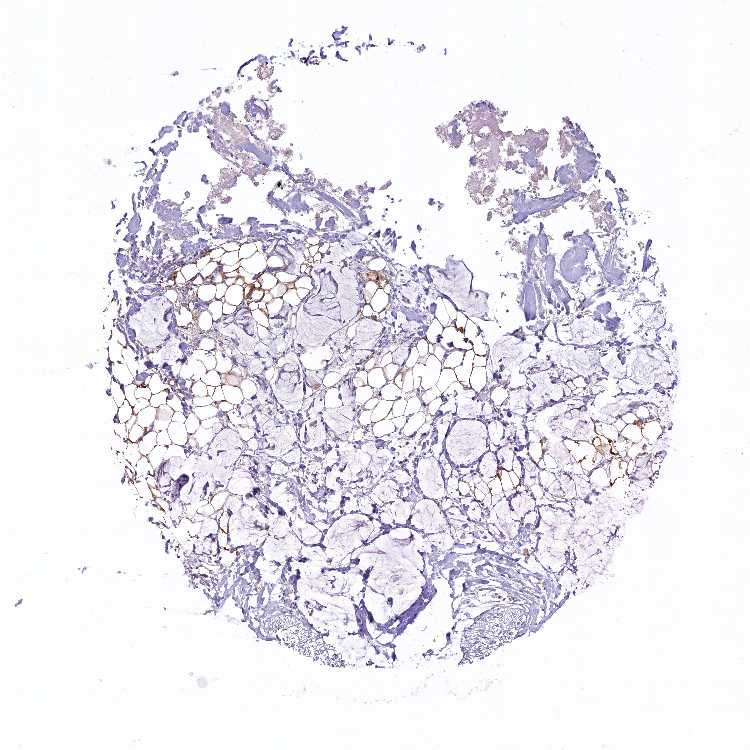

SOFT TISSUE 2 - Antibody stainingi

Antibody staining in the annotated cell types in the current human tissue is reported as not detected, low, medium, or high, based on conventional immunohistochemistry profiling in selected tissues. This score is based on the combination of the staining intensity and fraction of stained cells.

Each image is clickable and will lead to virtual microscopy that enables deeper exploration of all samples and also displays staining intensity scores, fraction scores and subcellular localization as well as patient and tissue information for each sample.

Antibody HPA041409Antibody HPA041482

Fibroblasts MediumLow

Peripheral nerve Not detectedNot detected